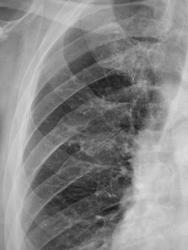

Справа консолидированнные переломы задних отрезков 6-7 ребер, далее произошло развитие избыточной костной мозоли. далее сформировался ложный сустав между ними, далее образовался неоартроз. Правые отделы сердца выглядят увеличенными в мпервую очередь за счет разворота больного. В боковой проекции добовляет ощющение снижения прозрачности легочной ткани обызвествление передней продольной связки позвоночника с образующимися косстными анкилозами на уровне тел ТН7-ТН10.

Подозрительно долго этот случай держится на первой полосе. Неужели Валентин Львович какую-то свинью подсовывает? Что это за кругляк на фоне левого предсердия, оно и есть? Или нисходящая аорта танцует ламбаду? Или в S9 что-то есть? Наверное, нельзя долго смотреть на снимки (как и на картины), можно "поехать". Первое мнение самое правильное.

Игорь Иванович. Именно, круглая тень справа привлекает сразу внимание. Когда был выставлен только обзорный снимок в прямой проекции, подумал о кисте, липоме в передне-нижнем средостении. Не исключал и осумкованный посттравматический выпот, так как у больного с этой стороны следы перелома ребер. Мечтал о патологии в заднем средостении. Ждал, что выскажутся коллеги, хорошо знающие сердечную патологию в рентгеновском отображении. Но все обсуждение было направлено на ребра и я оставил ветку. Больного отпустили домой, как Вы хотели.

Вообще то -это не левое а правое предсердие